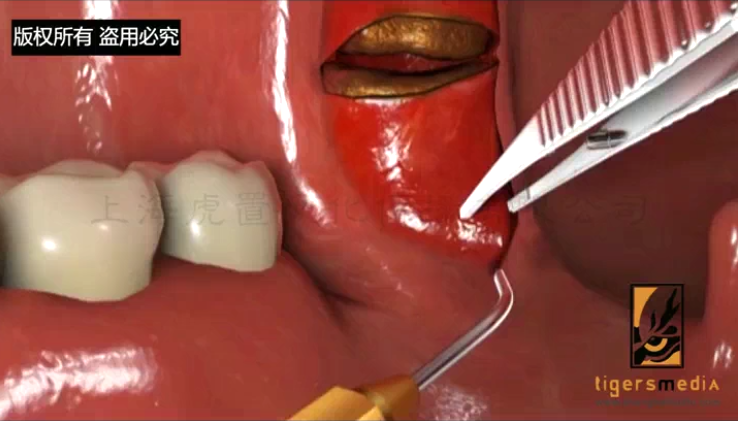

- > 医学手术动画有哪些优势-虎置文化集团2026-03-02

- > 医学三维动画有哪些特点和优势-虎置动画2026-01-13